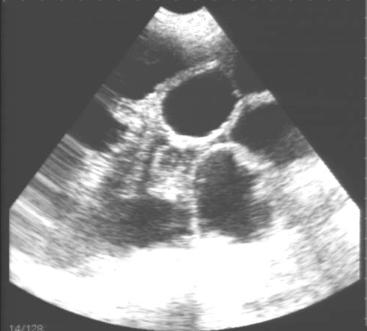

3 配种后25~28天内的做好妊娠诊断,可使用试纸或B超对妊娠猪进行妊娠诊断,有条件的猪场对于B超在4周不能确定的,可以在6-7周再次确定。同时结合经验判断:在正常情况下,配种后21天左右不再发情,且表现为:贪睡、食欲旺、易上膘、皮毛光、性温驯、行动稳、阴门下裂缝向上缩成一条线等特性的母猪,即可确定妊娠。

图1-1 B超诊断示意图

图1-2 B超诊断妊娠状态示意图